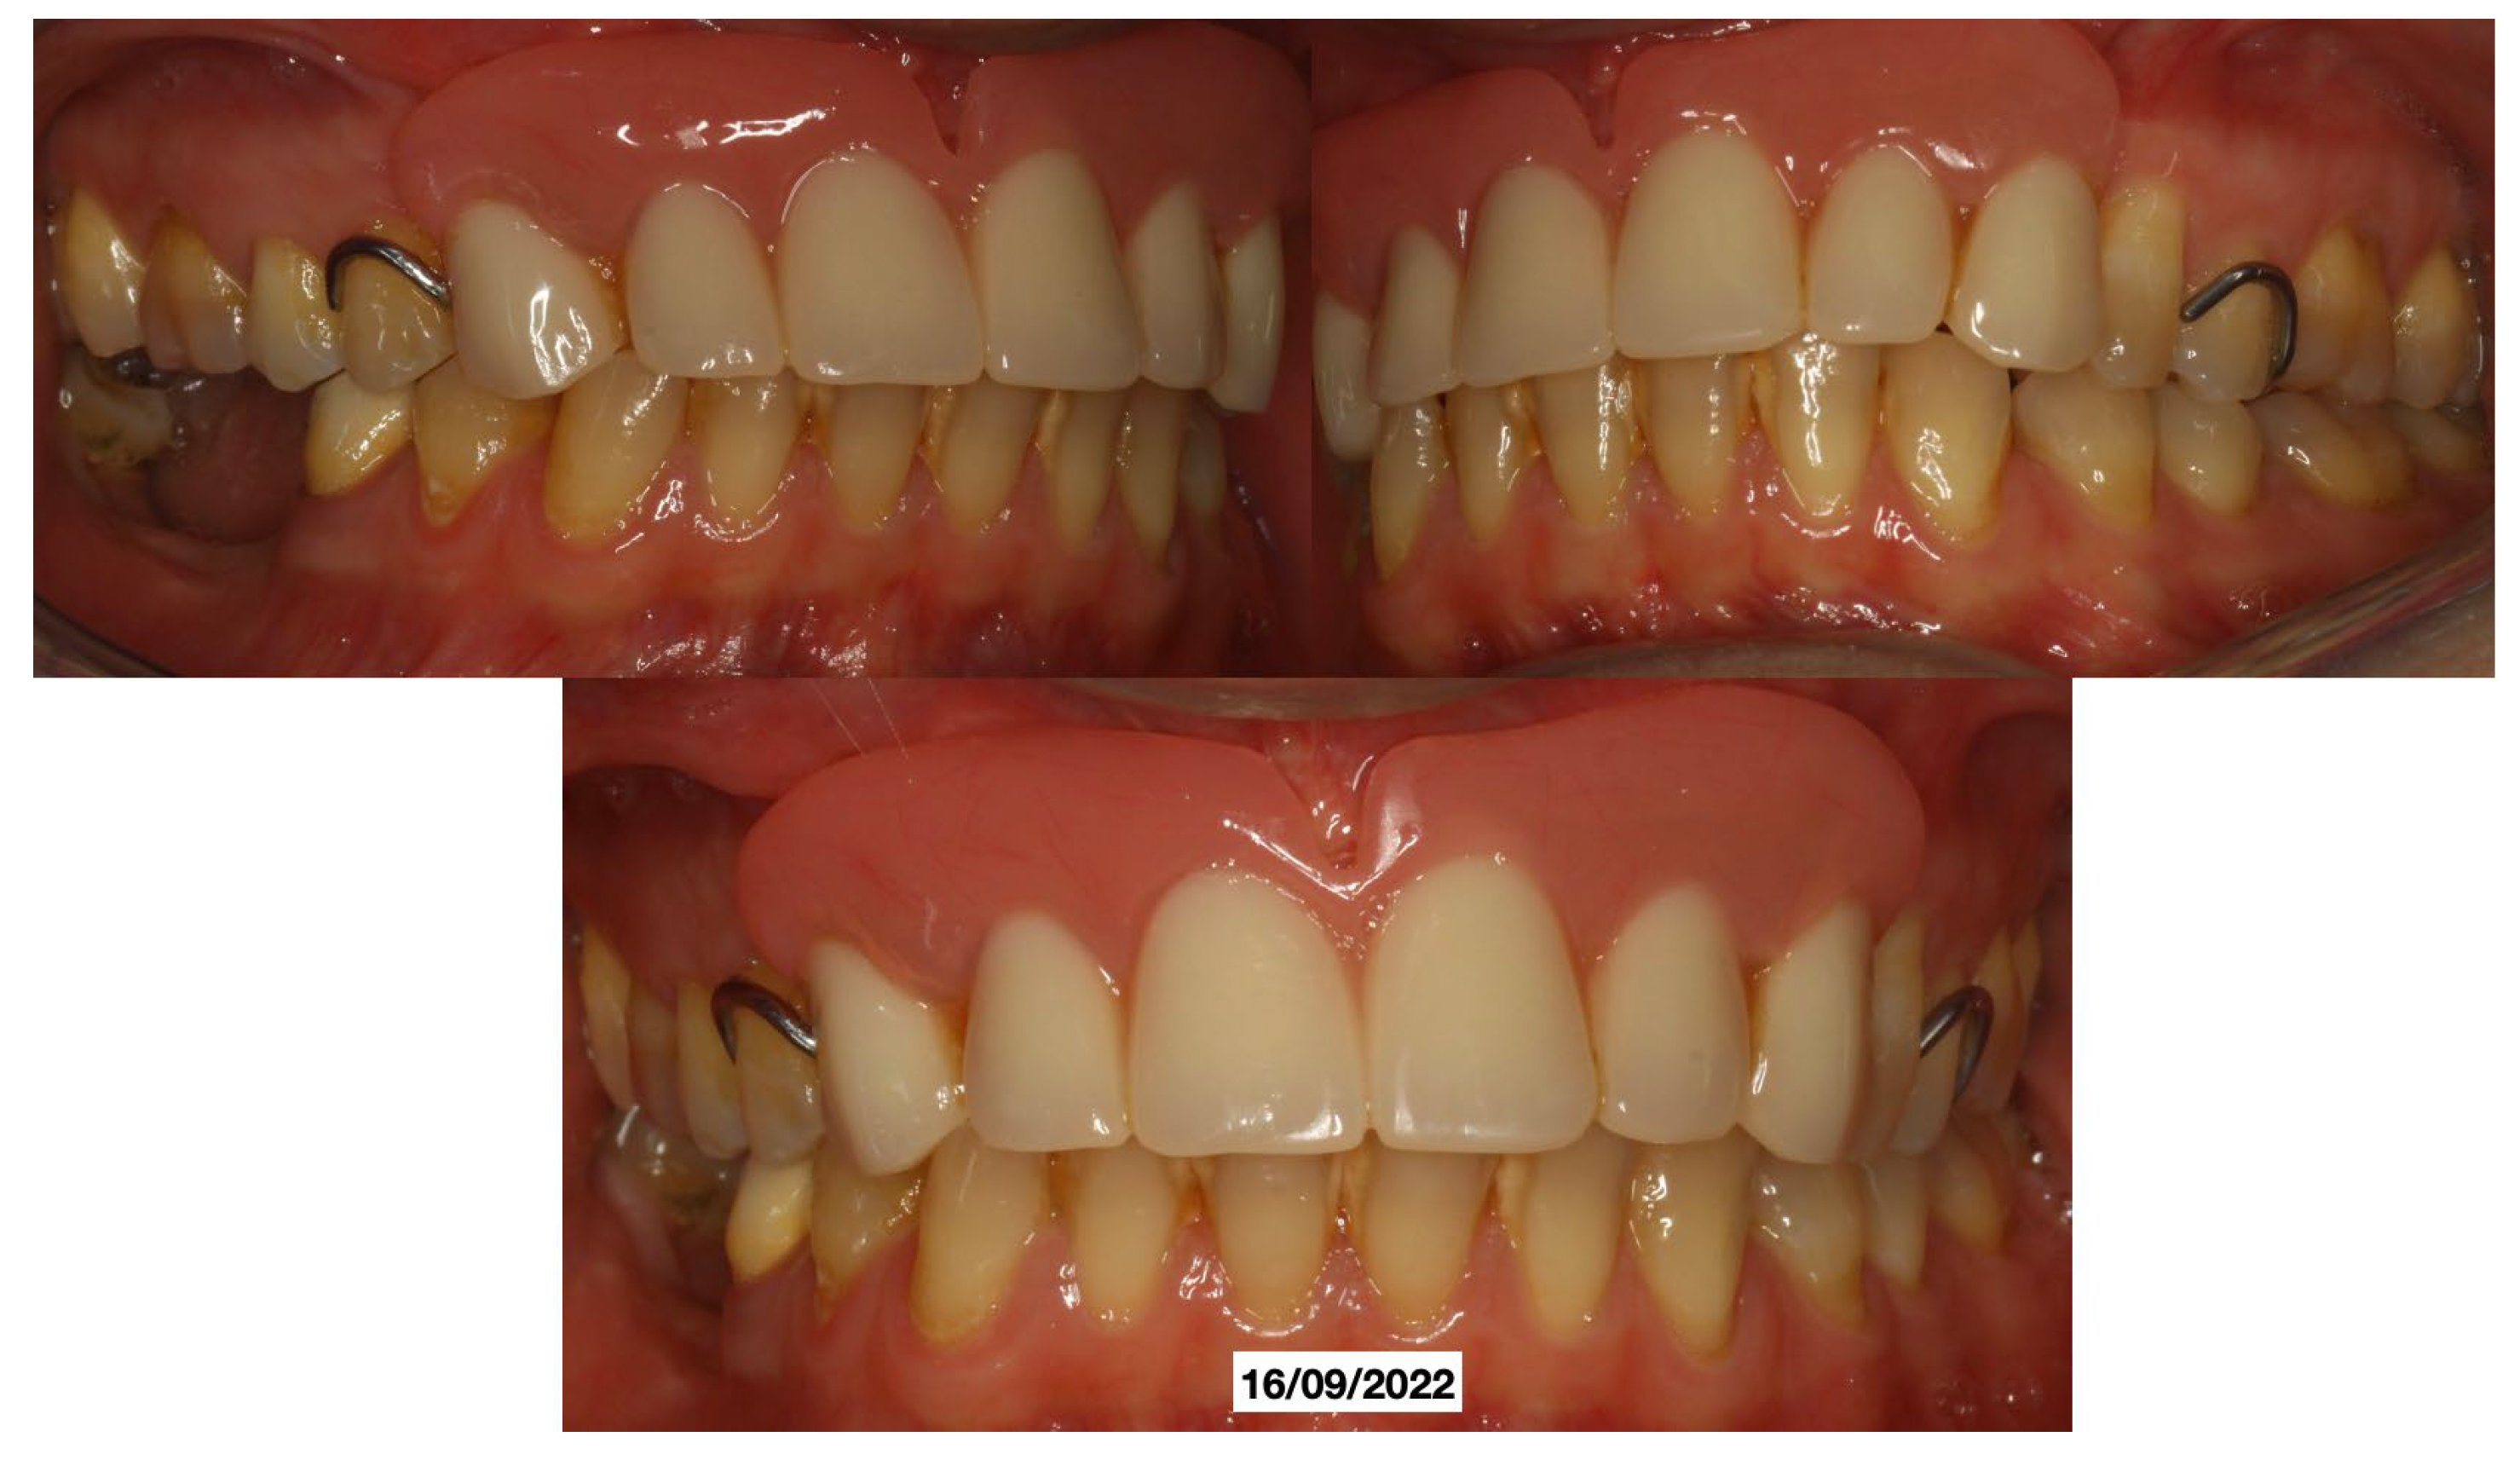

It was decided to temporarily rehabilitate the edentulism with a fixed partial denture after preparing 23-12-13 (Figure 4), keeping the adjacent teeth under observation but with a slight radiolucency already present.

In June 2024, the implants were inserted in areas 16 and 17. Three months after the insertion of the last implants in 16-17 (4.2 × 10 mm and 4.2 × 8 mm, Biotech Dental, Allée de Craponne, Salon de Provence, France), it was possible to proceed with the digital impression-taking to proceed with a temporary prosthesis in PMMA (Figure 9) after a radiographic control (Figure 10).

Figure 9. Fixed prosthetic rehabilitation.